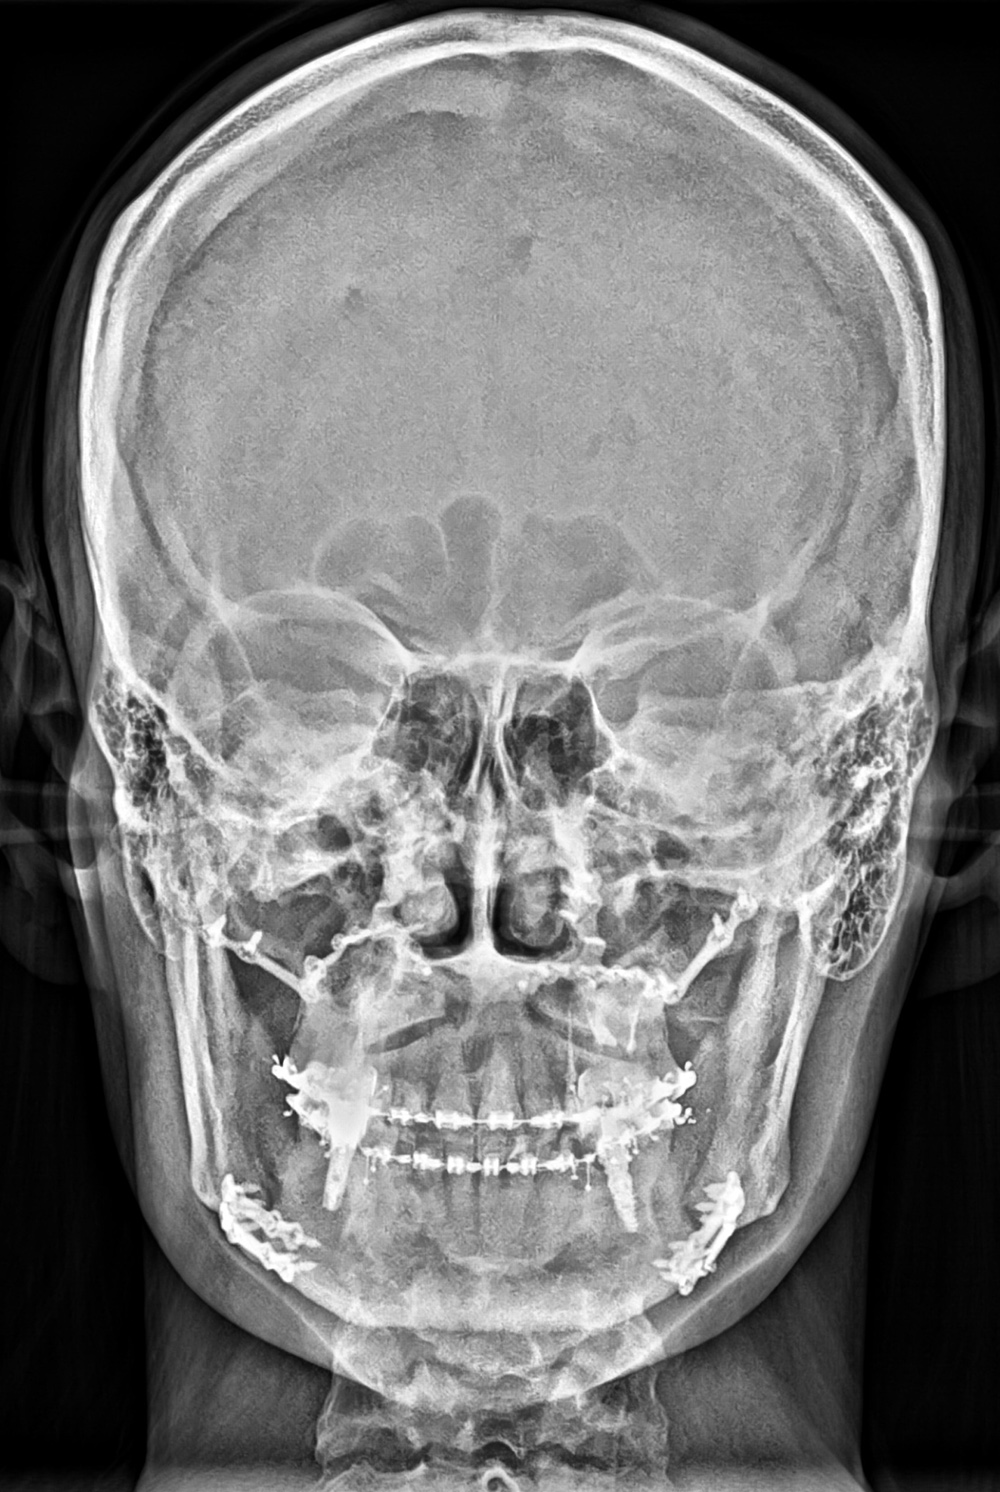

Panorâmica especial para ATM;